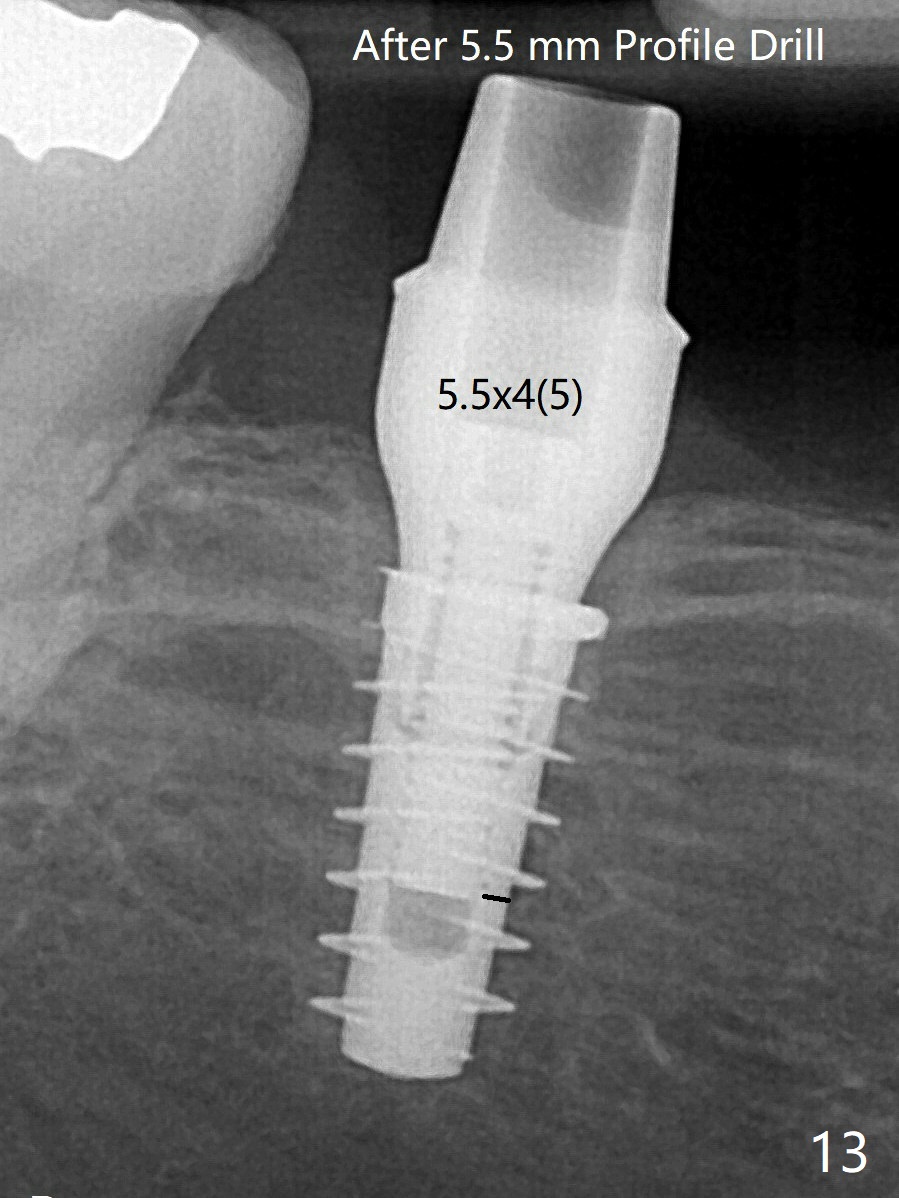

改用5.5x4(5)毫米UF(不同品牌)基台,临床上不能就位,局麻使用5.5毫米Profile Drill后,才能就位(图十三),螺丝下端超越最低螺沟(横线)。